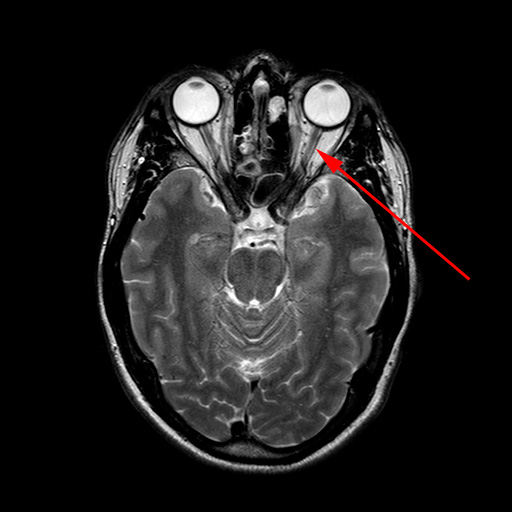

Øjne, normal, MR

Horisontalt snit fra en MR-scanning på højde med øjnene

Ovenfor ses en MR optagelse i form af et tværsnit gennem hovedet på højde med øjnene. Den røde pil peger på synsnerven i den ene side.